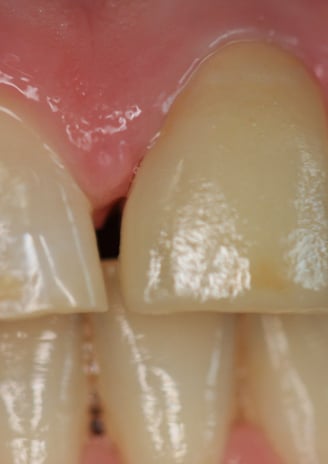

2. Sostituzione del Perno Moncone

Il perno moncone preesistente è stato rimosso e sostituito con un perno in fibra di vetro. Questo materiale offre vantaggi significativi:

Elasticità simile alla dentina naturale, riducendo il rischio di fratture radicolari.

Elevata adesione ai materiali compositi, garantendo una maggiore stabilità della ricostruzione.

Radiotrasparenza, permettendo un migliore controllo radiografico nel tempo.

3. Preparazione del Moncone e Impronte

Una volta completato il trattamento endodontico e posizionato il nuovo perno, il moncone è stato preparato con una forma ottimale per la ritenzione della nuova corona. Successivamente, sono state prese impronte digitali per la realizzazione della protesi definitiva.

Moncone ritentivo